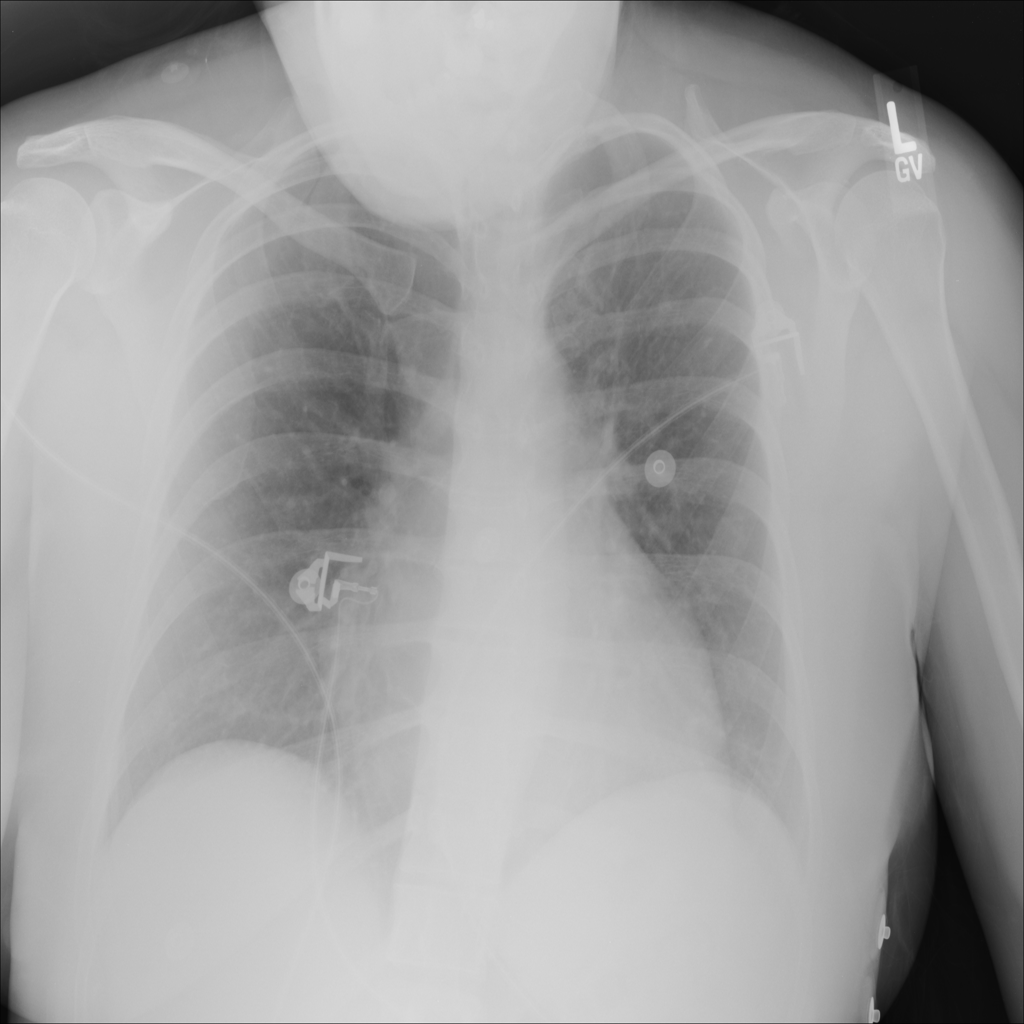

Pneumothorax

Pneumothorax means air is present outside the lung in the pleural space, which can allow part of the lung to collapse. It is an important imaging finding because the size and clinical impact can vary widely.

Showing up to 90 reference images for Pneumothorax.

PAT-4639 · IMG-020Pneumothorax

PAT-4639 · IMG-020

PA